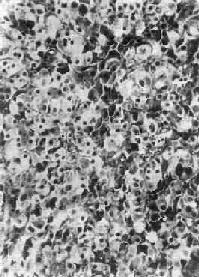

(二)肾上腺皮质癌

肾上腺皮质癌(adrenocortical carcinoma)甚少见,一般为功能性,发现时一般比腺瘤大,重量常超过100g,呈浸润性生长,正常肾上腺组织破坏或被淹没,向外侵犯周围脂肪组织甚至该侧肾。小的腺癌可有包膜。切面棕黄色,常见出血、坏死及囊性变。镜下分化差者异型性高,瘤细胞大小不等,并可见怪形核及多核,核分裂像多见(图15-17)。常转移到腹主动脉淋巴结或血行转移到肺、肝等处。分化高者镜下像腺瘤,如果癌体小又有包膜,很难与腺瘤区别,有人认为直径超过3cm者,应多考虑为高分化腺癌。

图15-17 肾上腺皮质癌